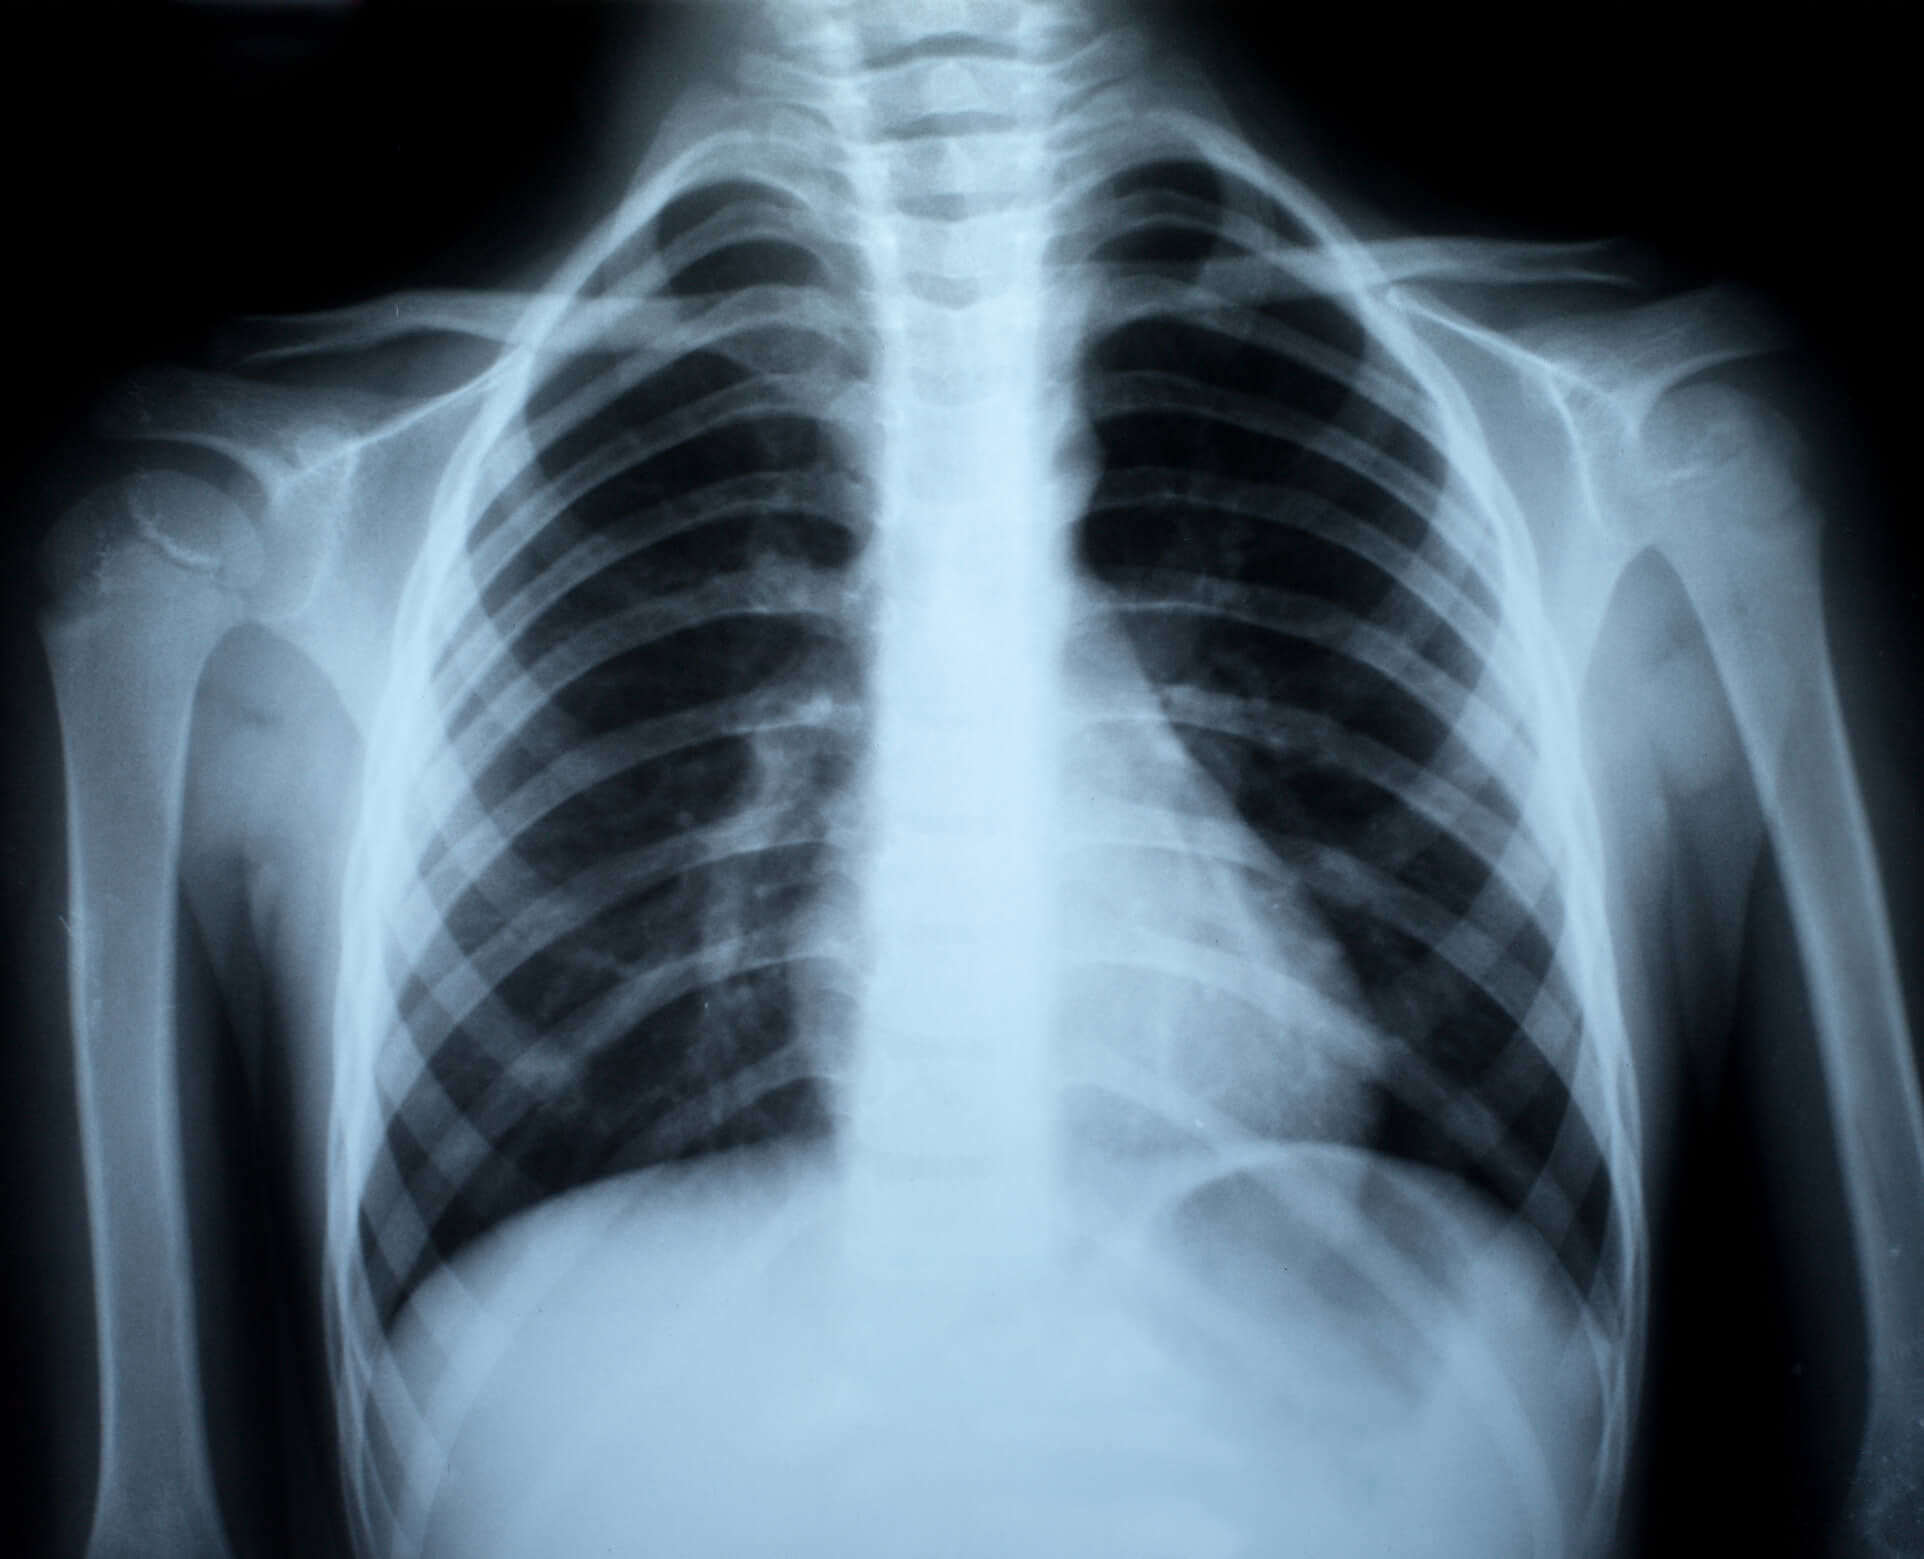

Rebra se lahko zlomijo pod vplivom sile na steno prsnega koša. Pri starejših osebah ali tistih z osteoporozo se rebra lahko zlomijo že ob manjših udarcih ali stiskanju (kompresiji) prsnega koša, kar običajno ne povzroči poškodb notranjih organov.

Pri mladih ljudeh, še posebej otrocih, je za zlom rebra potrebna večja sila, zato lahko ob tem pride tudi do poškodb pljuč ali drugih prsnih organov.

Klinična slika zloma rebra se kaže z bolečino, ki se poslabša ob globokem vdihu, pritisku na prsni koš, kašljanju in spreminjanju položaja telesa. Ob sočasni poškodbi pljuč lahko pride tudi do dihalne stiske.